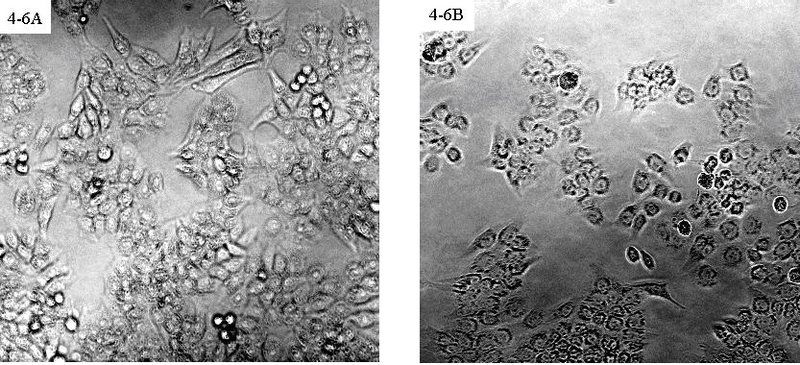

光学显微镜下观察到的Fuzhuanin B对HeLa细胞的抑制作用图(×200),图A是阴性对照,图B是用浓度为10μM Fuzhuanin B处理24 h后的细胞图片。通过比较图A和B可以明显看Fuzhuanin B对HeLa细胞具有抑制性。

此外,从茯砖茶中还新分离出多种儿茶素衍生产物,这些儿茶素衍生产物具有多种生物活性,如Fuzhuanin A具有促进人干细胞生长和防止β类淀粉样蛋白质错误折叠的功能,Fuzhuanin B能抑制HeLa细胞(人宫颈癌细胞)活性。茶褐素在抗氧化、降血脂、降血糖等方面有着良好的功效。这些儿茶素衍生物是安化黑茶渥堆和“发花”过程中产生的个性化特征成分,是安化黑茶独特风味品质与保健功效形成的关键成分之一。